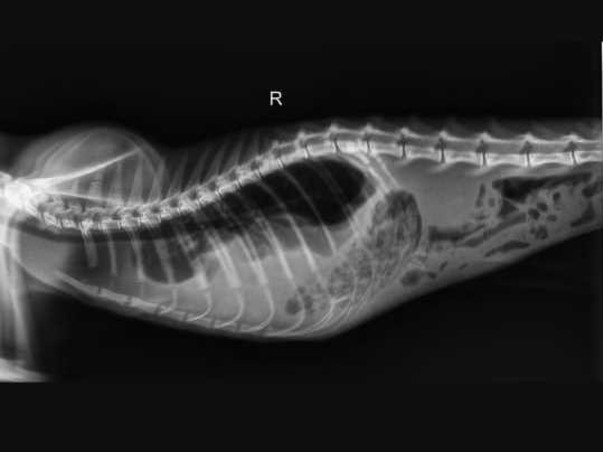

After emergency examination, blood tests, X-rays, ultrasound scans, and further imaging at Cessna Lifeline Veterinary Hospital, the doctors have confirmed that he is suffering from a diaphragmatic hernia.

A diaphragmatic hernia is a life-threatening condition where the muscle separating the chest and abdomen tears, usually due to trauma such as a fall or road accident. Because of this tear, abdominal organs move into the chest cavity and compress the lungs, making breathing extremely difficult.